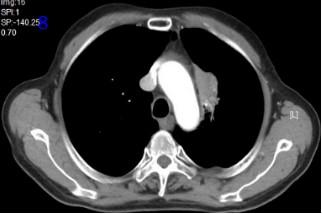

2022年10月18日再程放療后12個月復(fù)查胸部CT可見腫瘤較前縮?。▓D8),RECIST評價PR。

圖8再程放療后12個月胸部CT